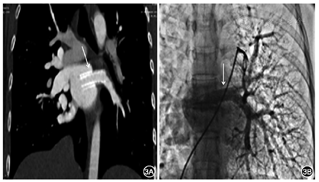

术后华法林长期抗凝[调整国际标准化比值(INR)1.5~2.0],并双联抗血小板治疗3个月。1年后随访,体重增加,症状和活动能力进一步改善,静息下经皮SaO295%,6 min步行距离为480 m。超声心动图示左肺静脉支架处血流正常,肺血管增强CT提示支架通贴壁良好,无内膜增生或充盈缺损,心导管示肺动脉压正常,肺动脉造影示左肺动脉血流明显改善,再循环左肺静脉支架通畅,无再狭窄(图3)。